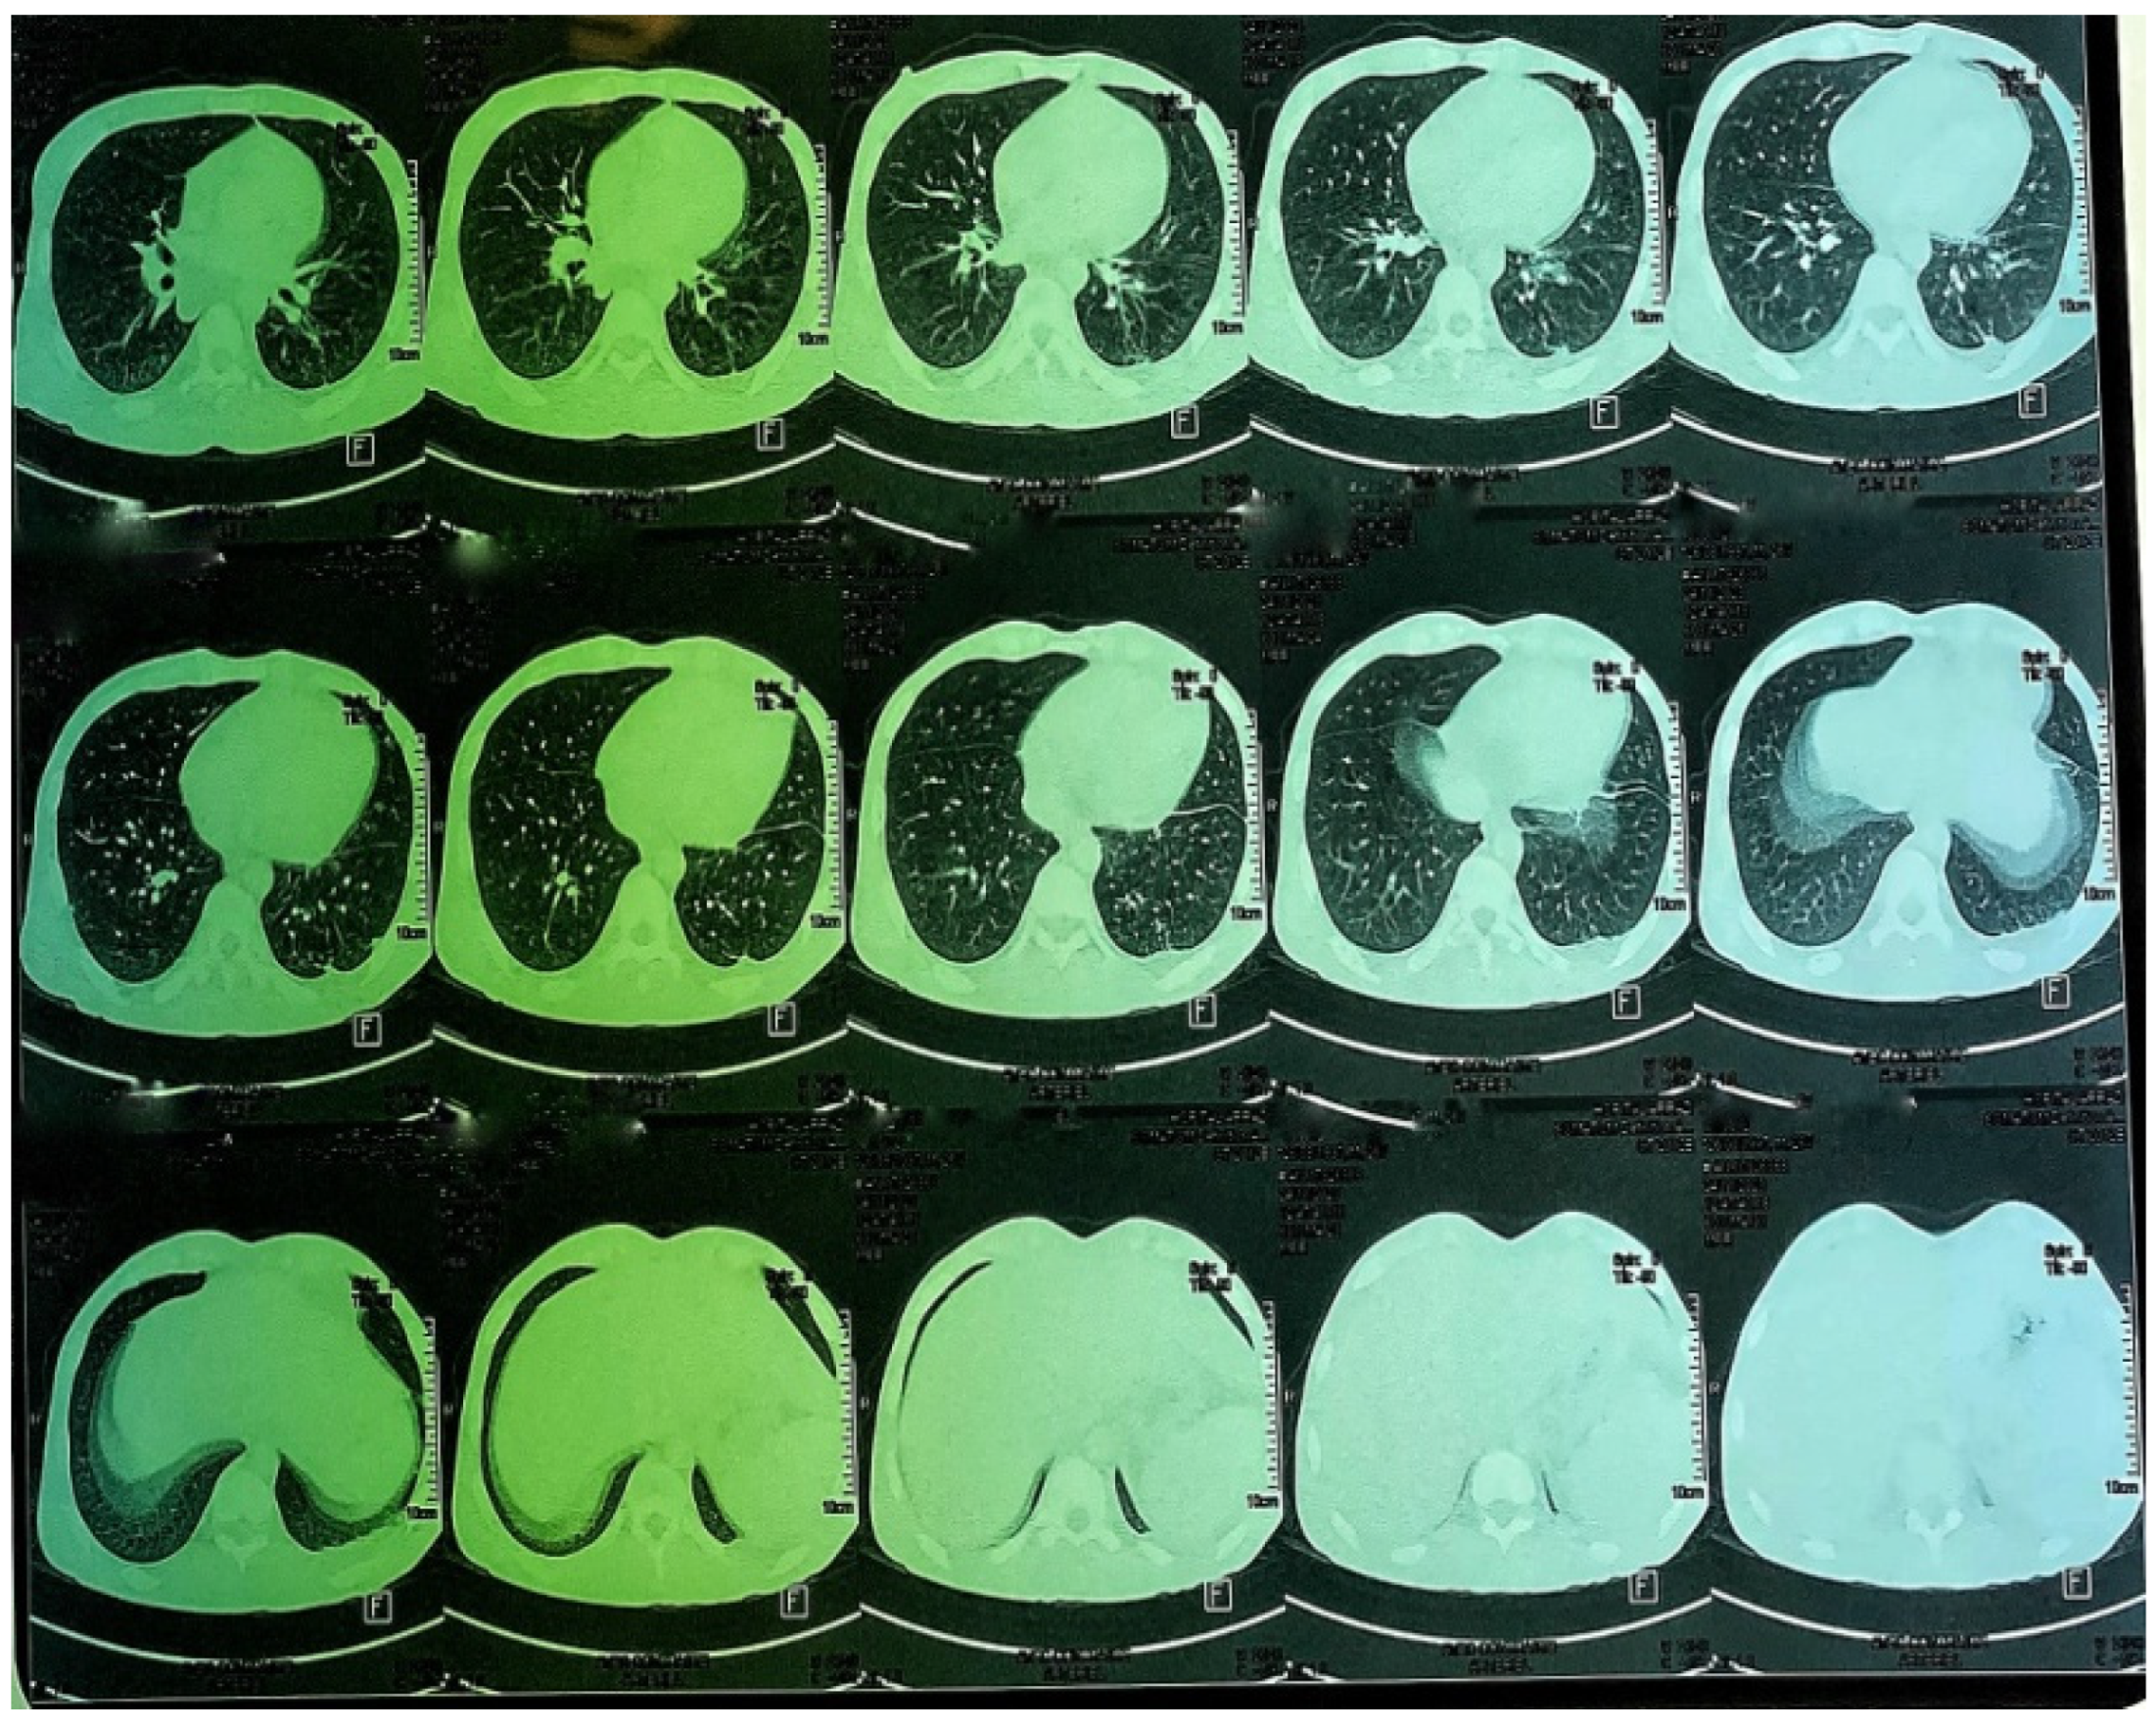

A CT scan of the chest, abdomen and pelvis was subsequently performed, showing a mild left pleural and abdominal effusion associated with right supra-diaphragmatic adenopathy and homogeneous hepatosplenomegaly (Figure 6 and Figure 7).

Figure 6. CT images of the thorax and abdomen:axial view.

Figure 7. CT images of the thorax and abdomen.